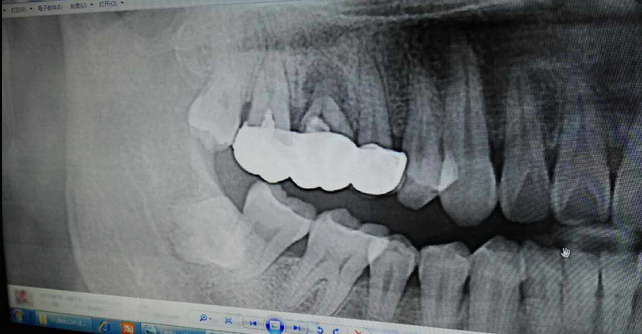

超聲牙周刮治案例

病例:患者男性47歲

右下8骨埋伏并且黏連;從根分叉處通過;有彈性;術(shù)中看到神經(jīng)束

實(shí)在找不到;近中牙冠沒去干凈